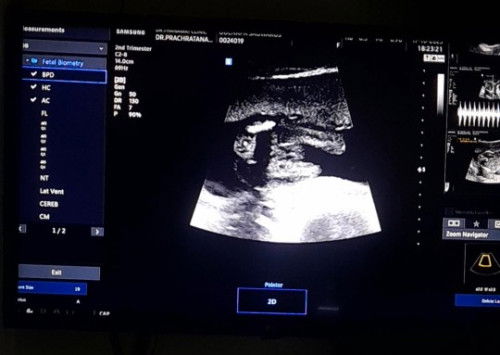

แม่ๆ ช่วยดูหน่อยได้ไหมคะะ แบบนี้เพศหญิงหรือชายคะ ซาวด์ตอนสี่เดือนหมอบอกเป็นหญิง กลัวย้ายทีมมากค่ะ หมอบอกว่ามีกรีบ

แล้วของเราเป็นกลีบชัดมากค่ะ แต่หมอยังไม่คอนเฟิร์มว่าเพศอะไร